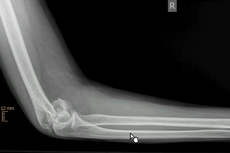

Ein stabiler Ellenbogenbruch (Olekranonfraktur), bei dem die Bruchstücke nur minimal voneinander entfernt liegen und keine Verschiebung aufweisen, kann nicht operativ (konservativ) behandelt werden. In diesem Fall wird der betroffene Arm im Gips oder in einer Orthese ruhig gestellt.

Ist dieses nicht der Fall und es liegt eine komplexe Fraktur mit verschobenen Knochenfragmenten vor, erfolgt in der Regel eine Operation. Durch den Zug der Streckmuskulatur klaffen die einzelnen Bruchstücke weit auseinander. Zur Fixierung der Fraktur und Wiederherstellung der Gelenkfunktion ist eine Verdrahtung oder Verplattung des Bruchs notwendig.